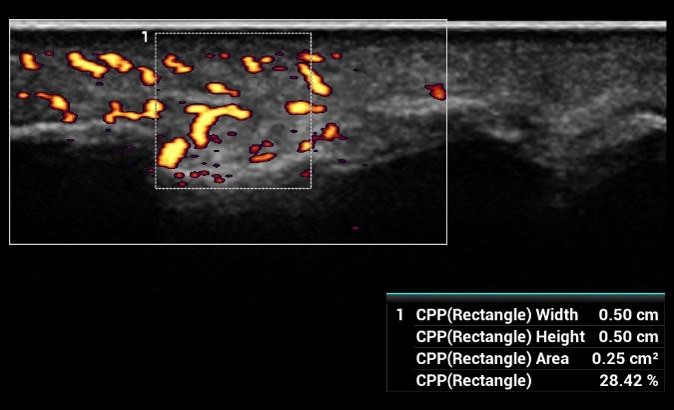

CPP - Percento farebných pixelov, výpočet percentuálneho podielu farebných pixelov v rámci definovanej oblasti záujmu

CPP: Vhodné na diagnostiku extrémne jemných prietokov (napr. reumatoidná artritída). Automatická štatistika percentuálneho podielu farebných pixelov v rámci vyšetrovanej oblasti.

CPP: Vhodné na diagnostiku extrémne jemných prietokov (napr. reumatoidná artritída). Automatická štatistika percentuálneho podielu farebných pixelov v rámci vyšetrovanej oblasti.

CPP: Vhodné na diagnostiku extrémne jemných prietokov (napr. reumatoidná artritída). Automatická štatistika percentuálneho podielu farebných pixelov v rámci vyšetrovanej oblasti.

CPP - Percento farebných pixelov, výpočet percentuálneho podielu farebných pixelov v rámci definovanej oblasti záujmu